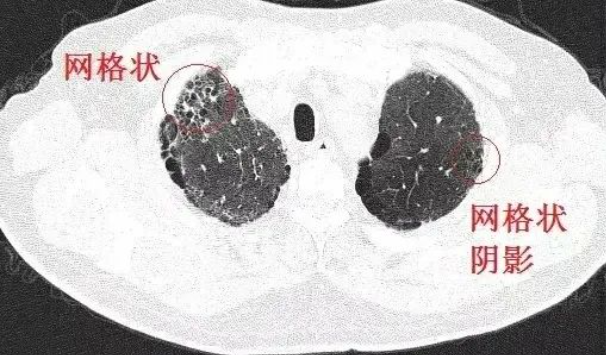

間質性肺病是指許多急性和慢性肺實質病變引起肺泡壁和肺泡腔不同程度的炎癥和纖維滲出,導致彌漫性肺間質纖維化發(fā)展的一組疾病。其病理變化可嚴重影響肺泡上皮細胞和毛細血管內皮細胞的功能和氣體交換,導致疾病晚期呼吸衰竭。

日常生活中最常見的間質性肺病包括各種職業(yè)性肺病,如肺塵埃沉著病、石棉肺和矽肺。 2019 年,中國科學院學者證實,人體內存在一種參與肺再生的肺多能干細胞。它可以根據需要“分化”,在肺部完成“跨界維持”,為肺部疾病的干細胞治療提供堅實的理論基礎。